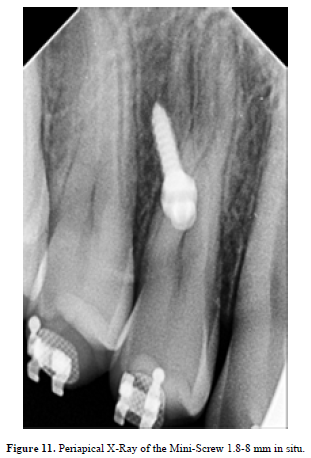

The Scissors-cross-bites a sort of flummox regarding orthodontic treatments, whereas the points of TADs proposed to be palatal most part in their treatments sequence.

TADs are of a paramount importance within treatment of scissors-bites (Figure 9,10), scheming the treatment plan is supposed to include the TADs pulling (Figure 11,12 & 13).